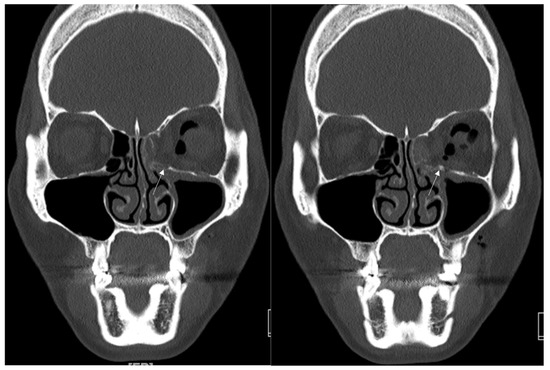

Figure 1. Case 1. Preoperative facial CT scan (coronal view) of the 8-year-old male patient with left inferomedial orbital wall fracture. The fracture sites were designated with white arrows.

An 8-year-old boy came to our emergency room with nausea, vomiting, bradycardia, and lethargy following a left eyeball trauma hit by a baseball. The patient complained of severe pain and discomfort with eyeball movement (Figure 1). We surgically approached the inferomedial orbital wall fracture on the same day of the trauma. After the subciliary incision, the fracture was exposed. The titanium-reinforced porous polyethylene (TR-PPE) plate was placed on the fracture site using a single screw at the inferior orbital rim (Figure 2). The oculocardiac reflex was entirely gone immediately after surgery. The patient was discharged on postoperative day 2 with significantly improved pain and discomfort.